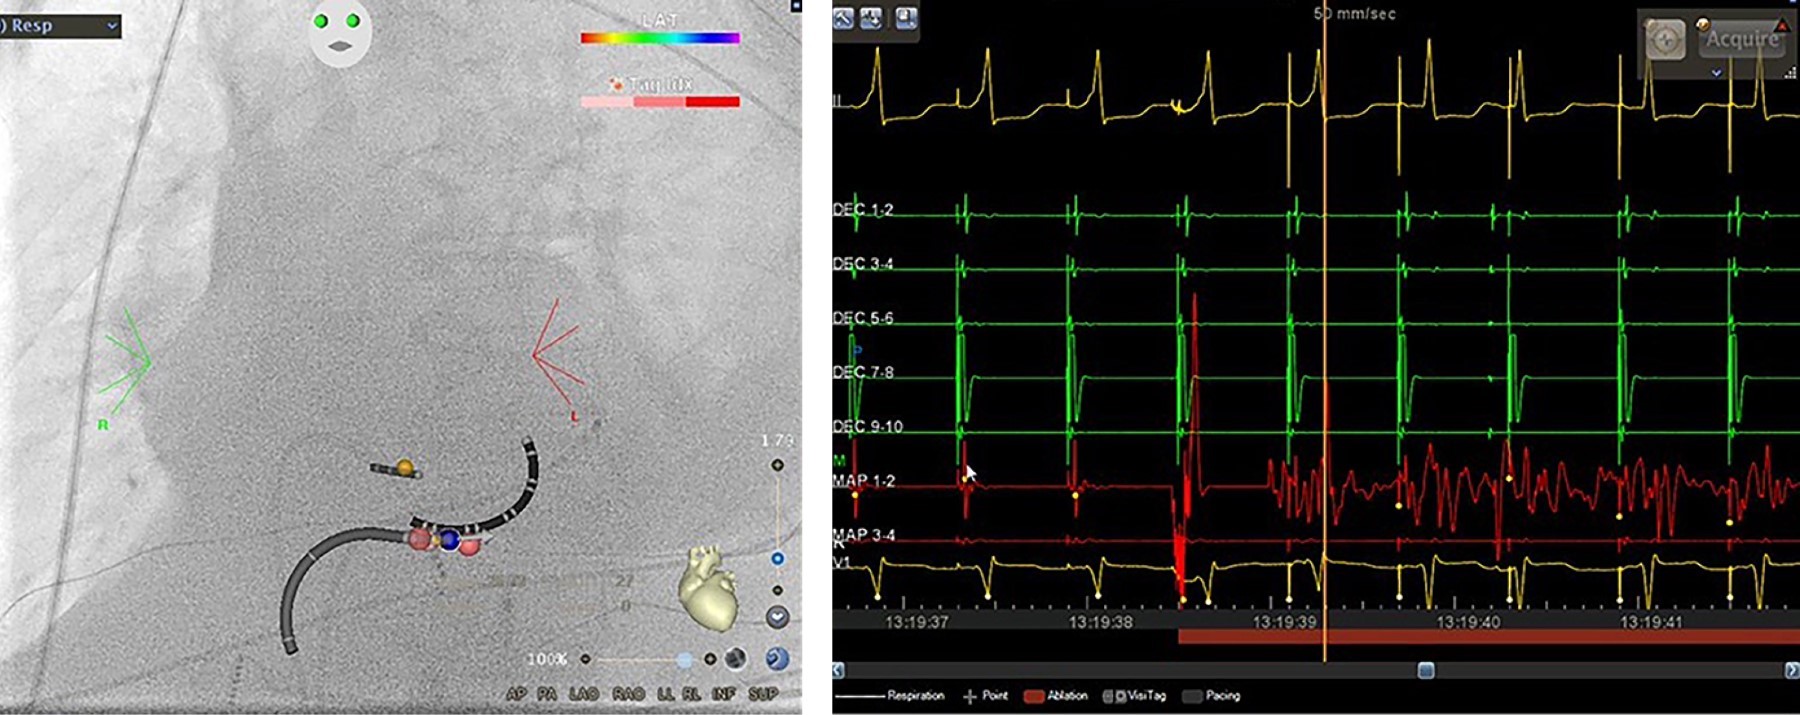

Reducción de la exposición a la radiación en un laboratorio de electrofisiología con el módulo CARTO-UNIVU™

La ablación por radiofrecuencia es una técnica eficaz y segura para el tratamiento de diferentes tipos de arritmias. La ablación por radiofrecuencia se realiza mediante fluoroscopia, una guía de navegación estándar, que está asociada con la exposición a la radiación y sus efectos nocivos bien reconocidos para los pacientes y para el personal de laboratorio. En la última década, los sistemas de mapeo electroanatómico han experimentado un fuerte desarrollo. A pesar de sus indiscutibles ventajas, no incluyen información obtenida por fluoroscopia en tiempo real. El módulo CARTO-UNIVU™ aborda esta importante limitación, ya que combina imágenes de fluoroscopia con el mapeo eletroanatómico tridimensional (3D) en una sola vista 3D, lo que permite una reducción pronunciada de la exposición a la radiación. Presentamos cuatro casos de nuestra primera experiencia en un solo centro con el nuevo módulo CARTO-UNIVU™.

Figura 3